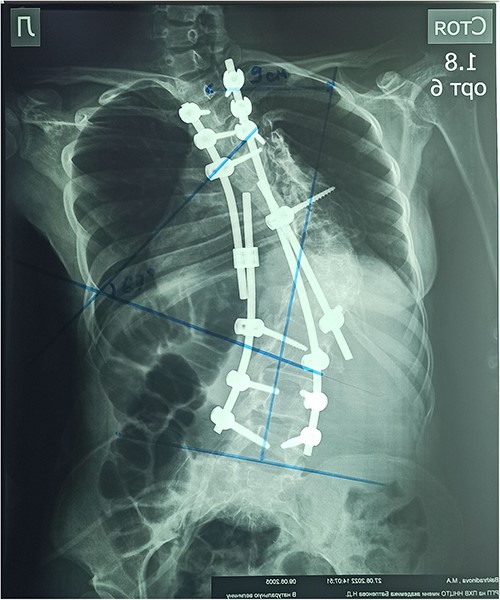

On the preoperative anterior–posterior X-ray, the Cobb angle was 110°; violation of frontal balance—13 cm (Fig. 2).

In the early postoperative period, the patient complained of moderate local pain. There were no neurological disorders on the periphery of the lower extremities. The function of the pelvic organs was normal. On the seventh day after the operation, the patient underwent a X-ray control. After surgery, the Cobb angle was 67°, the correction was 60.9%, and the frontal balance was 9 cm (Fig. 7).